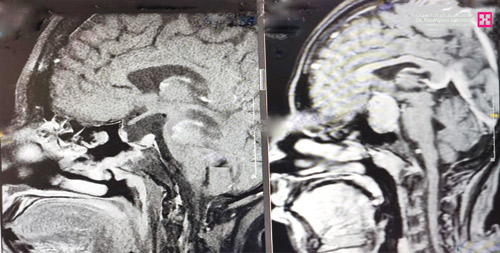

وكان المريض يعاني من أعراض، أبرزها صداع حاد وغثيان واستفراغ، وضعف وتشوش بالنظر، ثم تطور الأمر لاحقاً إلى فقدان الوعي، ووصل لقسم الطوارئ بحالة صحية معقدة، وأخضعه الفريق الطبي الذي قاده د. ناجي مسعود ود. الهيثم مصطفى استشاري الغدد الصماء، لفحوصات طبية دقيقة كشفت أنه مصاب بتدهور حاد في أملاح الجسم وقصور في وظائف الكلى، مع هبوط هرمونات الغدة النخامية، ونقص حاد في الصوديوم، إضافة إلى أن الصور الطبية أظهرت وجود ورم ضخم ضاغطاً على الغدة النخامية والعصب البصري.

وذكر د. مسعود قائلاً إن الفريق شرع في خطة علاجية متكاملة تم فيها أولاً إعادة الأملاح في الجسم إلى المعدل الطبيعي، ثم أجريت عملية سريعة للمريض عبر تقنيتي المجهر والمنظار وتم استئصال الورم بشكل كامل وتحرير الغدة النخامية والعصب البصري، ومضت العملية وفقاً للخطة العلاجية وتكللت جهود الفريق الطبي ولله الحمد بالنجاح، ونقل المريض إلى العناية المركزة بحالة صحية مستقرة، ثم تم تحويله إلى العناية المركزة أمضى فيها «5» أيام تحسنت خلالها حالته الصحية بسرعة مع العناية الطبية الحثيثة، غادر بعدها إلى منزله مشياً على قدميه. وقد أكدت صور أشعة الرنين المغناطيسي والأشعة المقطعية بعد العملية استئصال الورم بالكامل، كما أن المريض تخلص من كافة الأعراض التي عانى منها قبل العملية وعاد لممارسة حياته بصورة طبيعية.